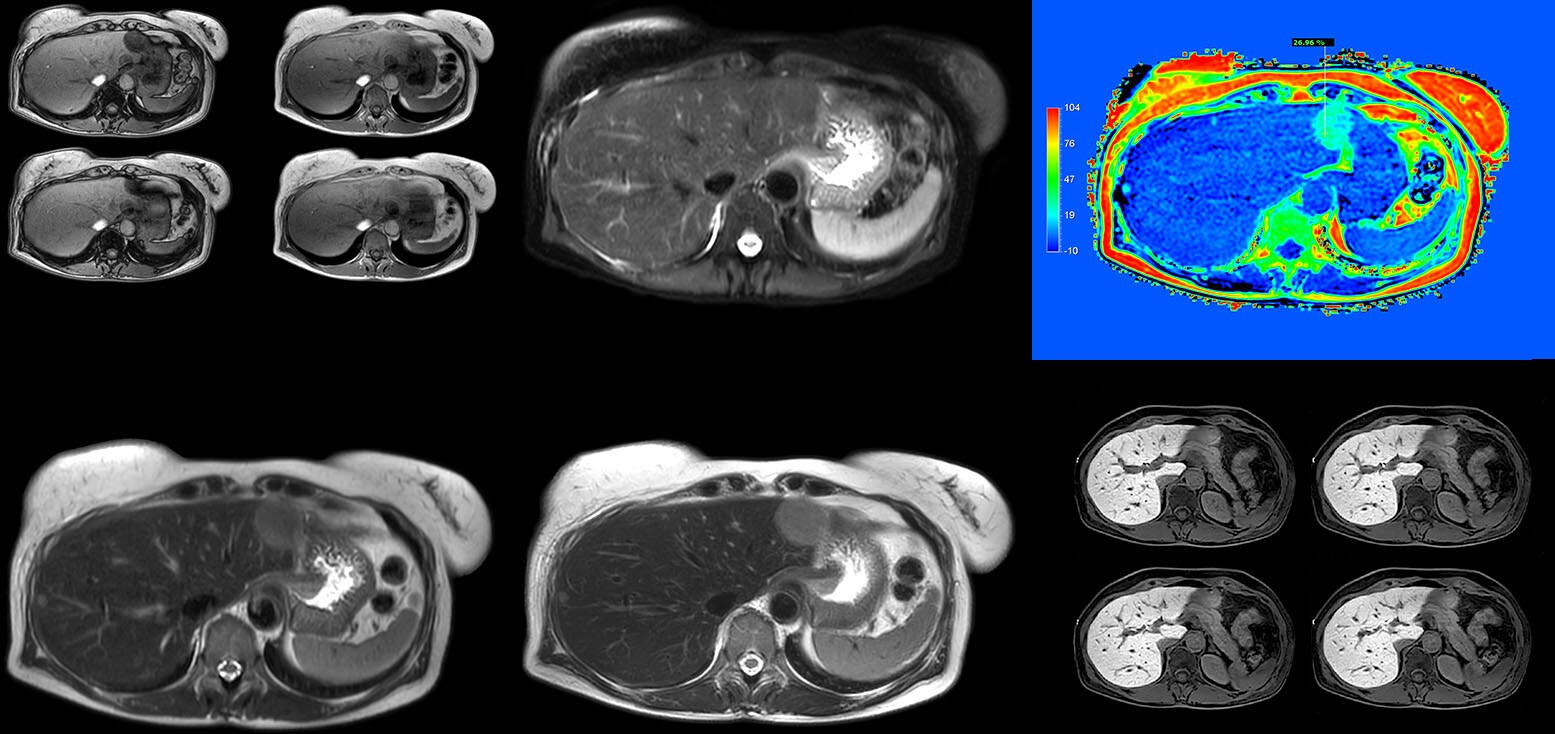

2. Magnetic resonance imaging

Magnetic resonance imaging

Patient-centric MRI equipment and solutions

At Philips, our mission is to enable fast, fully automated, and personalized MR exams for every patient while acting responsibly toward our planet and society. Through AI-driven smart connected imaging, optimized workflows, and integrated clinical solutions, we improve your MR department’s productivity, enhance the experience for both patients and staff, and deliver high-quality diagnostic outcomes.